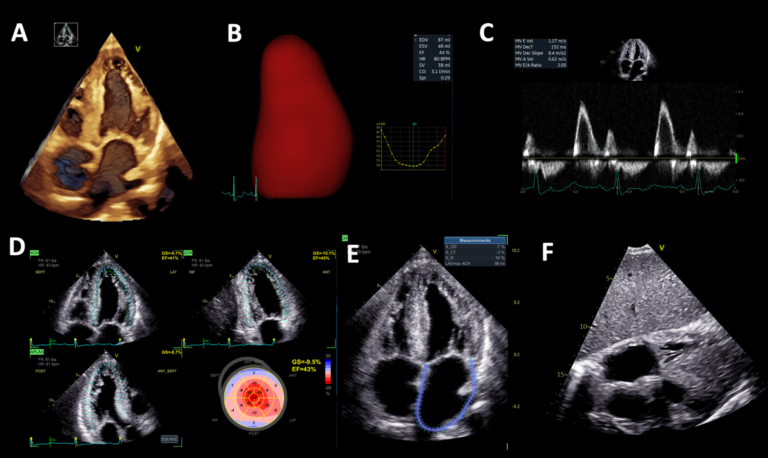

🫀 RISCONTRO OCCASIONALE DI TROMBO IN AURICOLA ATRIALE DESTRA IN UN GIOVANE PAZIENTE CON SCOMPENSO CARDIACO CONGESTIZIO E IN RITMO SINUSALE🫀